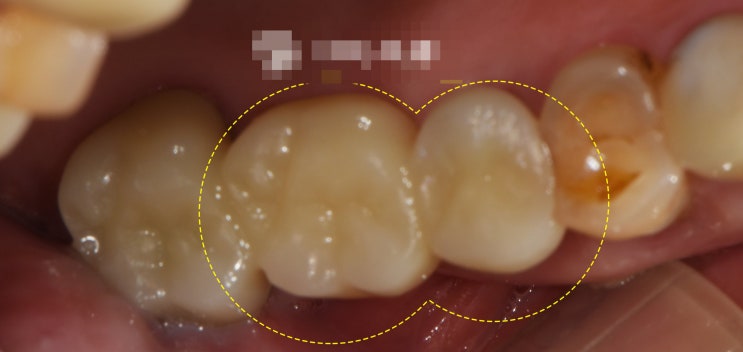

신촌역치과 정기검진의 중요성 다수의 충치 재발, 인레이, 신경치료

안녕하십니까, 대표원장 조민기입니다. 여러분들께서는 정기검진 을 받으신지 얼마나 되셨나요? 많은 분들...